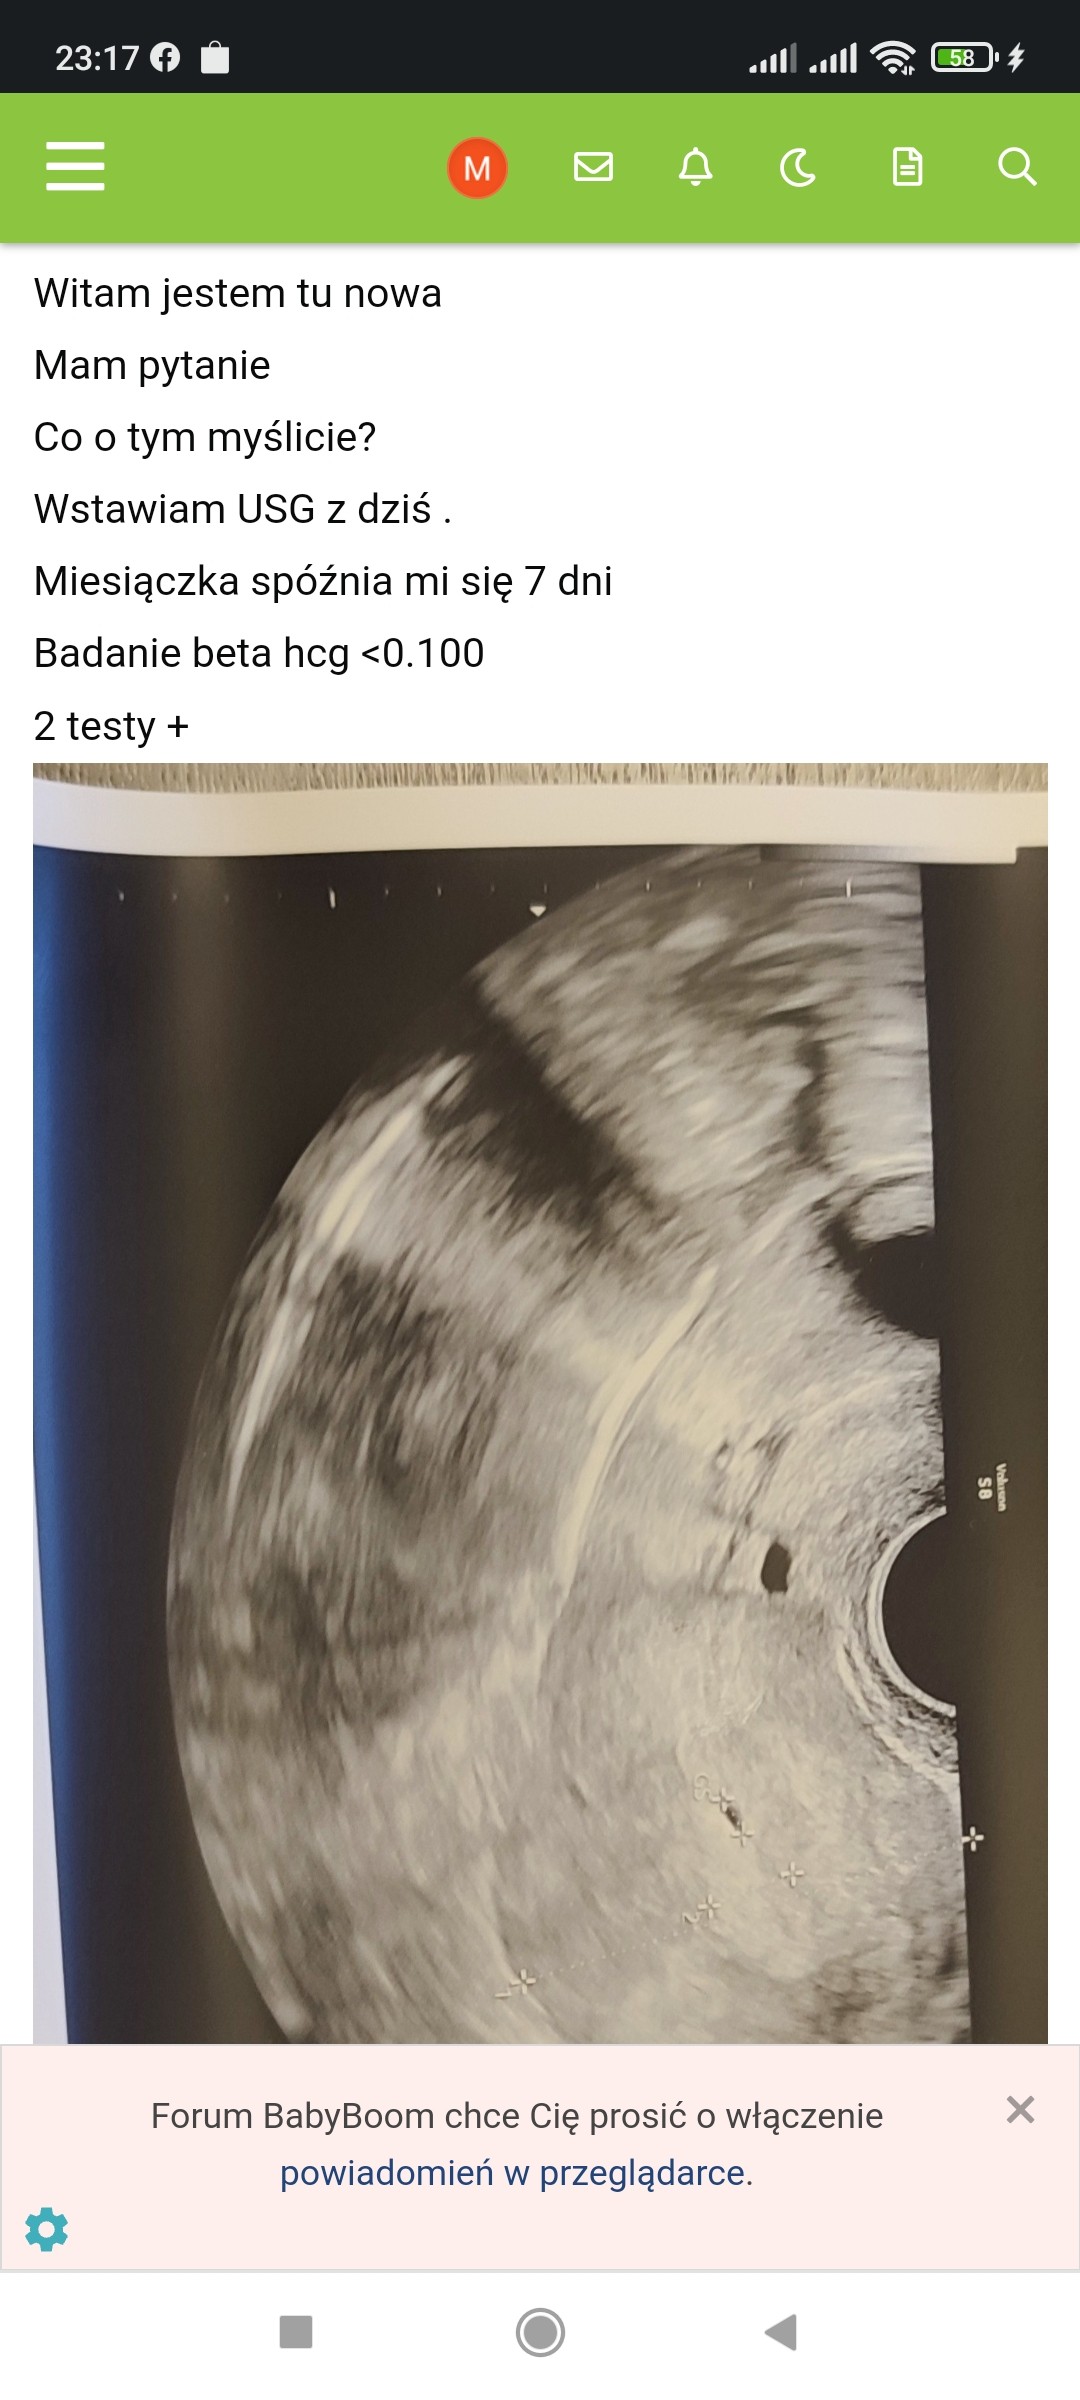

Screenshot_2022-04-07-23-17-04-036_com.android.chrome.jpg